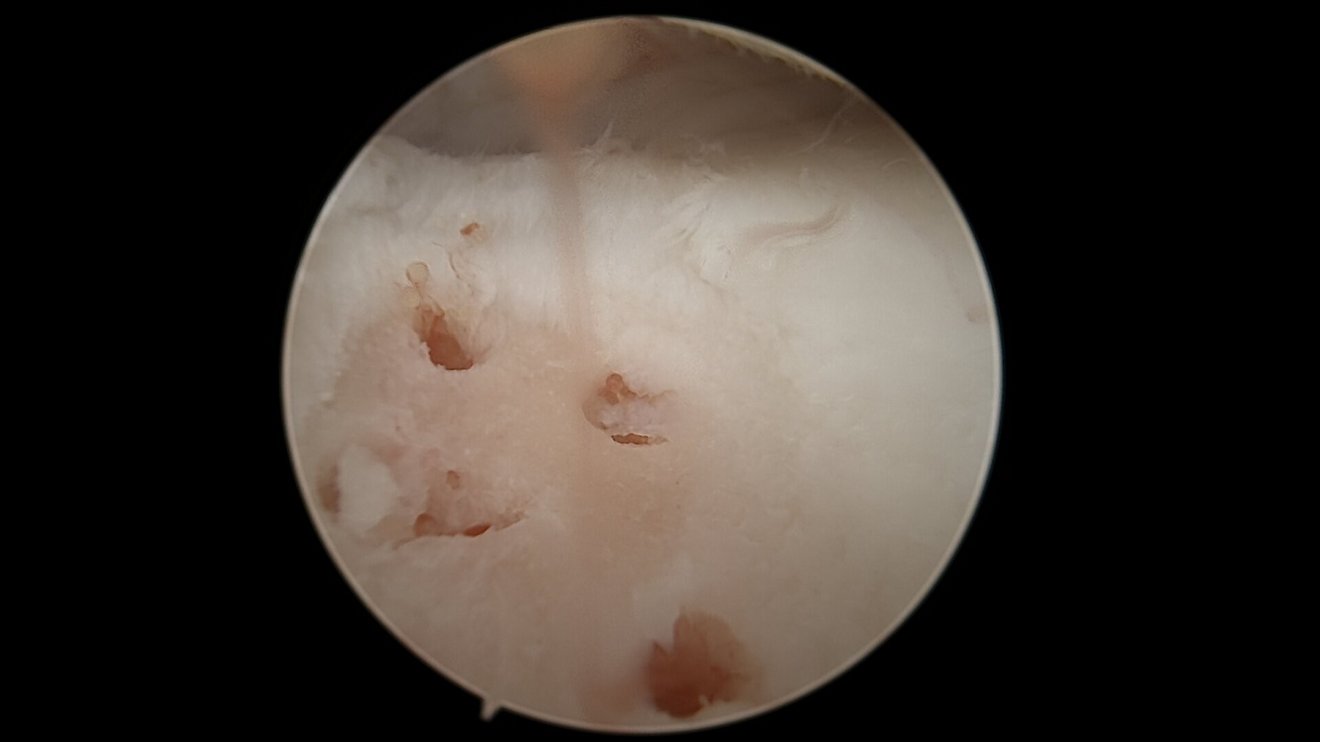

Als Behandlungsmöglichkeiten für Knorpelschäden gibt es die sog. Abrasionschondroplastik / Mikrofrakturierung, bei der der defekte Knorpel bis auf den Knochen abgetragen und dieser dann mit kleinen Löchern perforiert und ggf. mit einer speziellen Membran bedeckt wird. Durch die Perforationen tritt Knochenmark in den Defekt ein und es bildet sich ein sog. Regeneratknorpel. Auch die Möglichkeit einer Knorpelzelltransplantation (sog. „ACT“) wird bei uns angeboten. Hier werden in einer ersten Operation Knorpelzellen entnommen und in einer zweiten Operation in den Defekt eingebracht (entweder als sog. ACT Inject in einer Suspension oder als ACT 3d auf einer Membran). Auch die körpereigene Transplantation eines Knochen-Knorpel-Zylinders (OATS / Mosaikplastik) ist eine Therapiemöglichkeit, die wir anbieten können.